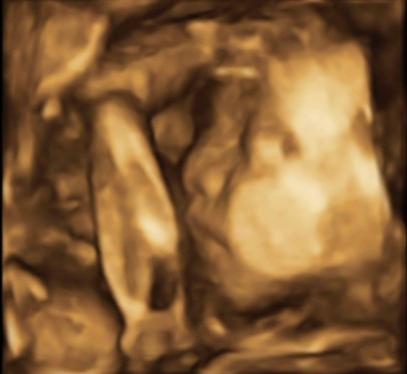

Zobacz załącznik 555316Zobacz załącznik 555317

No więc jest dwóch chłopów na 100% i to jaki kawał chłopów! Obaj srednio po 1111g gdzie na tym etapie powinno byc z 900ja nie wiem jak ja ten brzuch udzwigne jak będą rosnąć w takim tempie

no i ważą całkiem sporo, ale ja myślę, że przy bliźniakach to akurat plus, bo przeważnie rodzą się wcześniej, więc dobrze, żeby mieli wagę odpowiednią